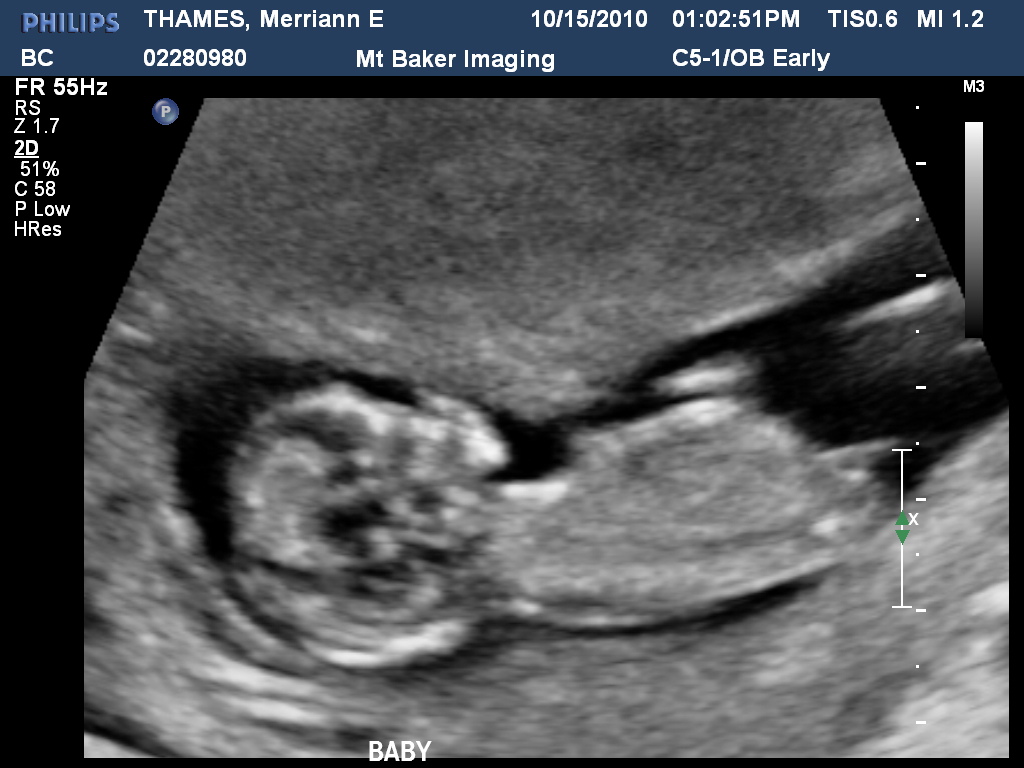

That’s right folks. We’re having a baby! I am due April 27. I had no idea how far along I was so we headed in for an ultrasound. I was already already over 12 weeks! Not that I hadn’t known at all. I have the constant nausea thing going on. But it is still nice when all things are confirmed and your 1/3 done. We looking forward to a spring baby. Warmer days, less bundling and another family member to share a spring B-day with Greg.